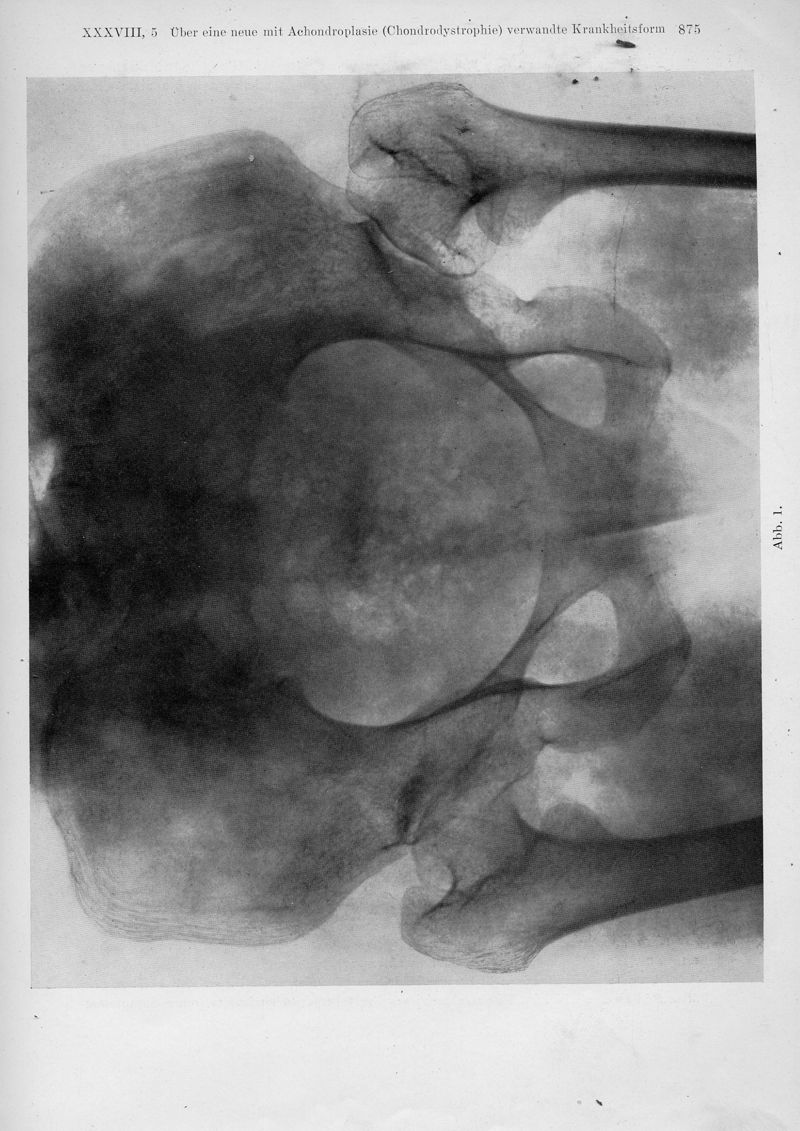

Über eine neue mit Achondroplasie (Chondrodystrophie) verwandte Krankheitsform. (Osteochondropathia multiplex Grudzinski, Achondroplasia atypica Silfverskiöld, Dystrophie spongieuse epiphysaire systematisée Ghimus)

In : Fortschritte auf dem Gebiete der Rontgenstrahlen, 1928, Vol. 38, pp. 873-82